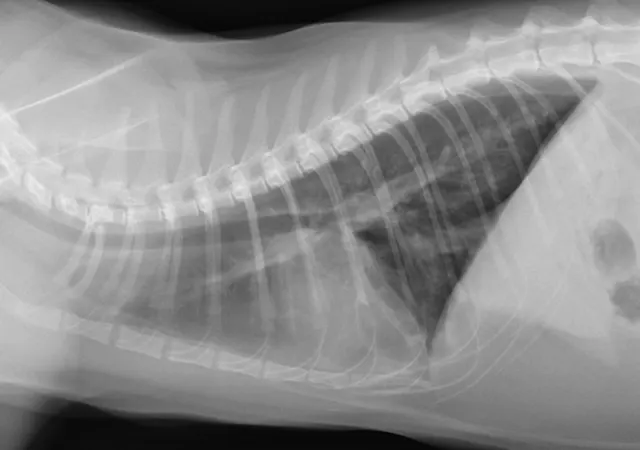

Thoracic radiographs showed lesions suggestive of heartworm or lungworm infection (Figure 1). An in-clinic heartworm antigen test was positive. The owners declined echocardiography.

FIGURE 1

Bronchointerstitial pattern in the caudal lung fields (A and B). Enlargement of the caudal pulmonary arteries is evident on the ventrodorsal (B) projection.